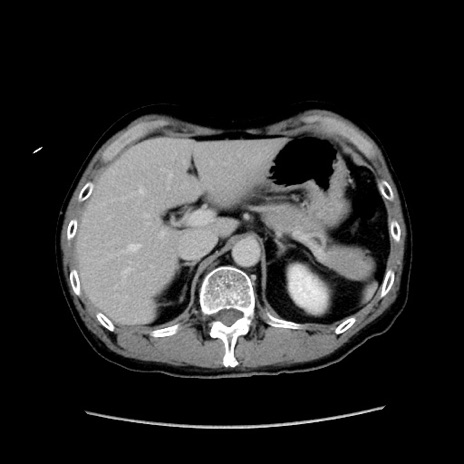

冠状断像